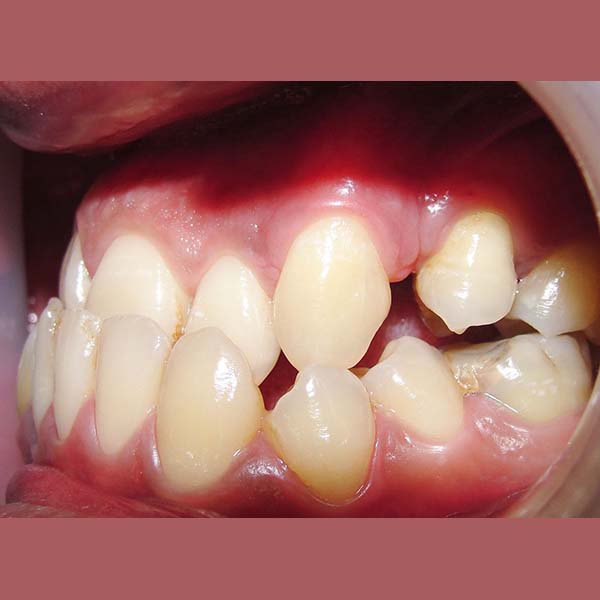

BEFORE

My young friend visited me suffering from a complete Bite collapse, a severe anterior crossbite, in addition to the loss of many of his back teeth. He was so frustrated, thinking that his case is incurable, and this frustration was reflected on his shy smile.